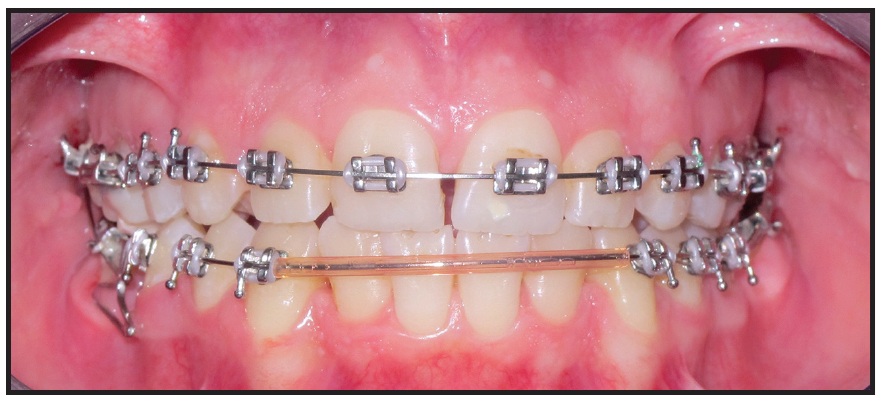

Brackets were repositioned and wire bends were added for final finishing and detailing of the occlusion (Fig. 10).

Fig. 9 After two months of third-molar uprighting and three months of space closure in both arches.

Fig. 10 Bracket repositioning for finishing and detailing of occlusion.

Interarch settling elastics were worn during this three-month period to maximize interdigitation (Fig. 11).

Total treatment time was 20 months. The patient finished with Class I canine and full-unit Class II molar relationships (Fig. 12). The upper first premolars were reshaped to resemble the canines. Radiographic records taken prior to debonding showed acceptable root parallelism, absence of significant root resorption, and satisfactory anterior dental inclinations (Table 1). Overbite and overjet were within normal limits, and an appropriate smile line was achieved.

Fig. 11 After three months of finishing, with interarch settling elastics worn to maximize interdigitation.

The upper first premolars were reshaped to resemble the canines. Radiographic records taken prior to debonding showed acceptable root parallelism, absence of significant root resorption, and satisfactory anterior dental inclinations (Table 1). Overbite and overjet were within normal limits, and an appropriate smile line was achieved.